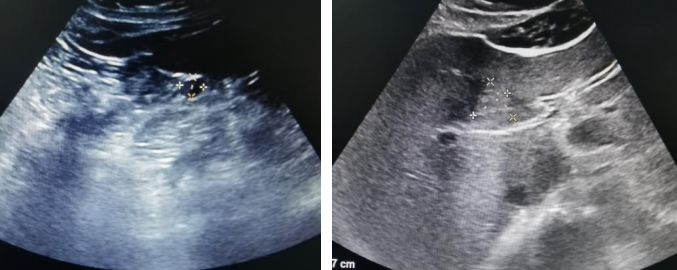

腹部超声(2024年4月11日):肝脏多发实性结节。

腹部超声(2024年4月11日)